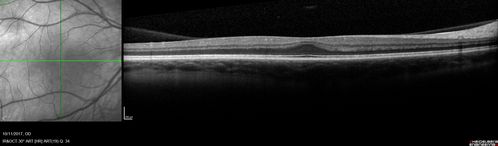

Foveal Hypoplasia in adult with ROP - good Vision

26 year old female Born at 1 lb 15 oz and had cryo for ROP at birth.

VA OD: Dcc20/25

VA OS: Dcc20/20

SD OCT shows foveal hypoplasia

The SD OCT scan shows incursion of one or more of the plexiform layers into the center of the fovea.